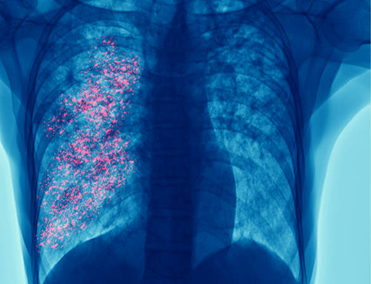

La infección por VSR puede propagarse al tracto respiratorio inferior y causar neumonía o bronquiolitis (inflamación de los pequeños conductos respiratorios que ingresan a los pulmones).

Los signos y síntomas pueden incluir:

Fiebre

Tos intensa

Sibilancias: un ruido agudo que generalmente se escucha al exhalar.

Respiración rápida o dificultad para respirar: es posible que la persona prefiera sentarse en lugar de acostarse.

Cianosis: Color azulado de la piel por falta de oxígeno.